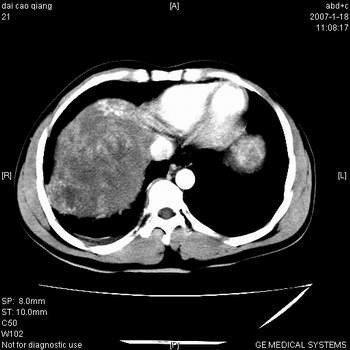

符合巨块型肝癌表现:

1、平扫低密度,增强后表现为快进快出。

2、动脉期可见迂曲的动脉供血血管

3、并可见门静脉右支癌栓形成

4、可见假包膜

5、腹主动脉旁结节影,考虑肿大淋巴结。

肝右叶巨大不均匀低密度肿块,前缘有假包膜,增强明显的呈快进快出表现,门脉右支有癌栓,病人虽然年轻但还是首先考虑肝右叶巨块形肝癌,病人血象高只能说有合并感染。不支持肝脓肿。